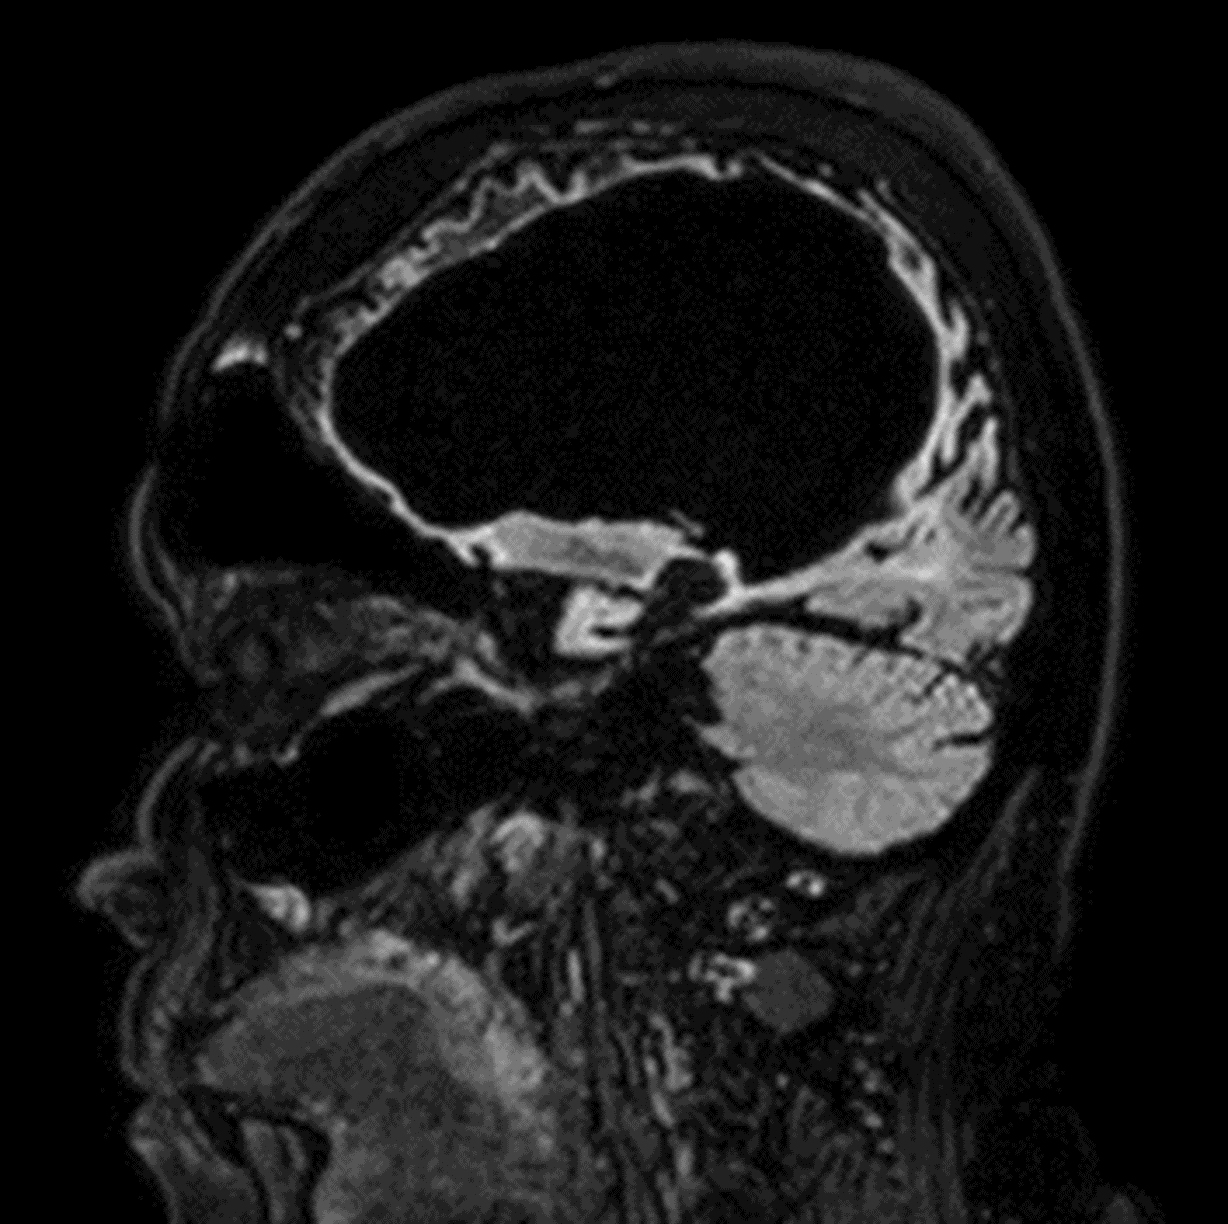

Brain lesion with Compressed SENSE

Sagittal T1w 3D TFE